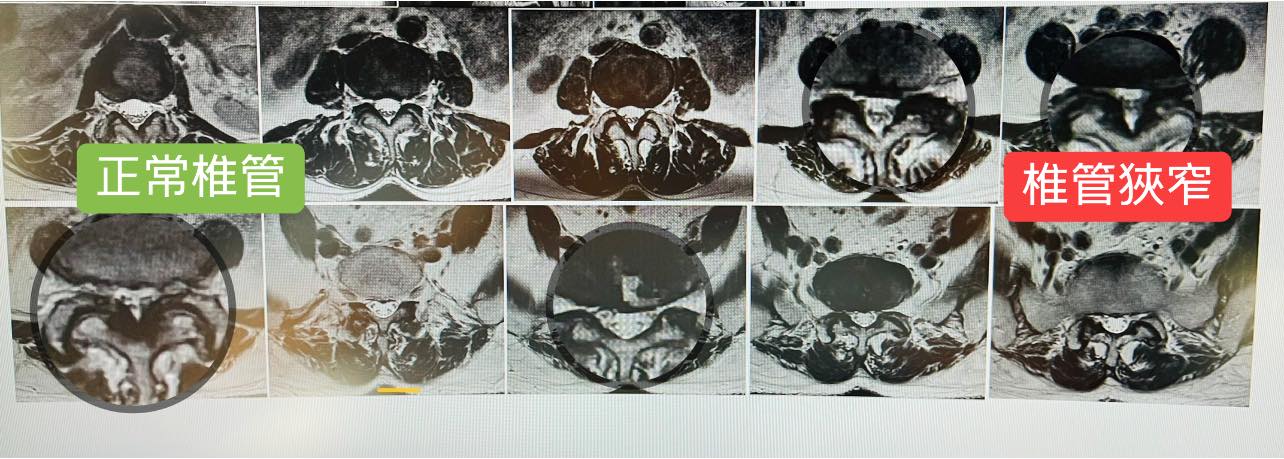

4️⃣核磁共振掃描 (MRI) – 核磁共振掃描對於評估脊椎的問題非常有用,因為它能顯示出神經、其他軟組織和骨骼。